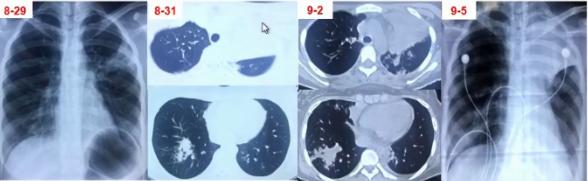

• 第1-3天:阿奇霉素治疗3天(口服2天+静脉1天)无效,胸片示左上肺及右下肺斑片影

• 第4-5天:头孢曲松+阿奇霉素+小剂量激素2天无效,肺CT示左上肺大片实变及右下肺斑片影

• 第6-7天:头孢曲松+阿奇霉素+甲泼尼龙40mg bid 2天仍无好转,出现呼吸困难,CT示肺内病变进一步增多,血常规7.8×109/L、N 82.9%,CRP 43.16 mg/L,动脉血气分析PH7.42 PaO246mg Hg。

• 第8-9天:美罗培南+利奈唑胺+甲泼尼龙 80mg/d,体温无下降,呼吸困难加重,吸氧8-10L/min,指脉氧80%左右,G试验154.7,加用伏立康唑,行气管插管机械通气,病情仍无改善转来我院。

图6 患者在院外胸部影像学变化。左上肺小块实变,逐渐累积至右下肺,而且左上肺实变扩大和膨胀不全。